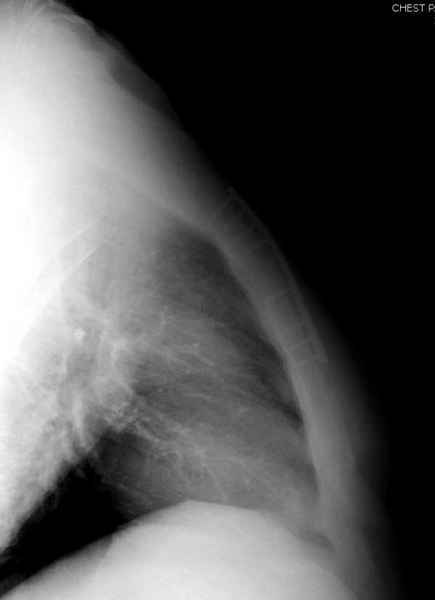

Юра, интересно, насколько такой остеосинтез контролирует степень репозиции, а то у меня имеются снимки девочки 11 лет, направленной ко мне на консультацию из одной из республик бывшего союза.

После торакальной операции, по-видимому, сильно натянули проволоку, и в результате получился захлест отломков в друг друга.

Оперировавший хирург предлагает подождать, а родителей беспокоит проблема прогрессирующей ассиметрии лица, как при кривошее.

А простые посттравматические ложные суставы грудины приходилось оперировать с ограничителем сверла и с фиксацией 2.4 мм пластинами с угловой стабильностью.